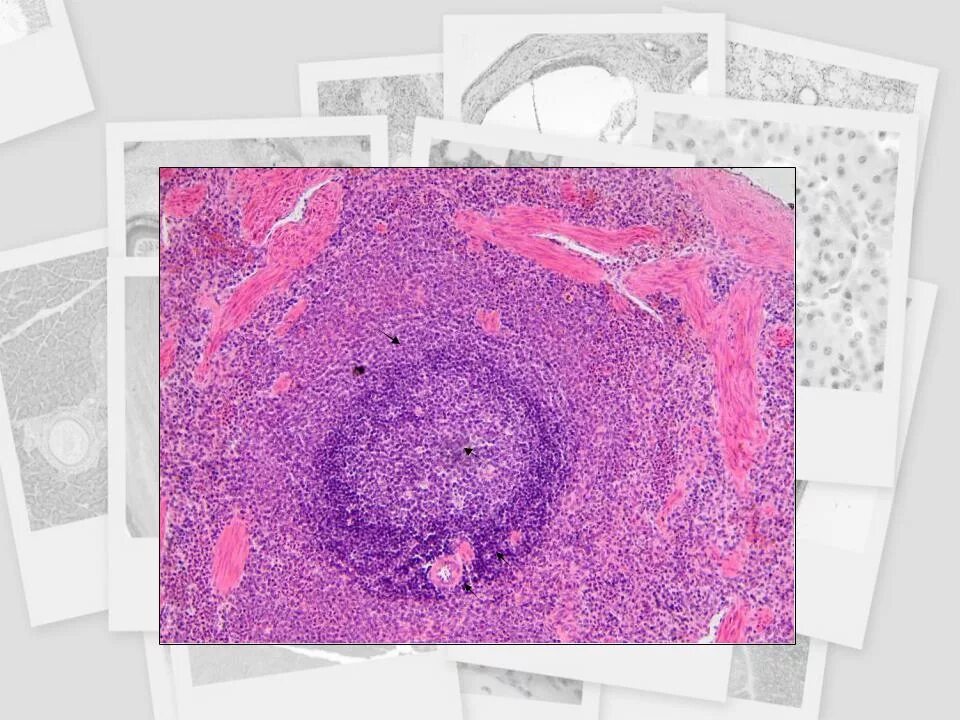

Окрашивание гистологического препарата